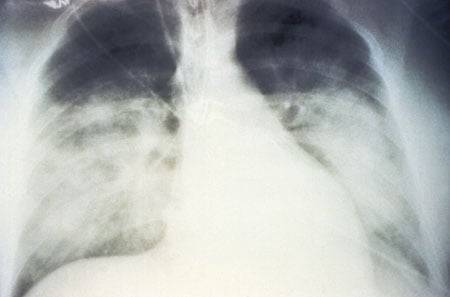

- Doctors usually diagnose HPS infections based on hantavirus lung symptoms are associated with rodents or probable contact with rodent-contaminated airborne dust, and chest X-rays provide additional evidence, but definitive diagnosis is usually done at a specialized lab or the U.S. Centers for Disease Control and Prevention (CDC).

HPS is a disease caused by hantavirus that results in human lungs filling with fluid (pulmonary edema) and causing death in about 38% of all infected patients.

Hantavirus apparently damages cells that compose blood vessel capillaries, causing them to leak fluids. This fluid leak, if it is profound in the lungs, causes the life-threatening pulmonary syndrome.